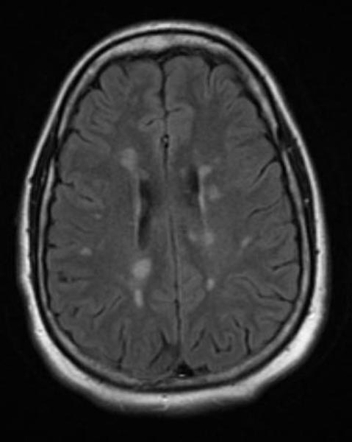

Esclerose Múltipla

A Esclerose Múltipla é uma patologia inflamatória crônica do Sistema Nervoso Central, acometendo desta forma o Encéfalo e a Medula Espinhal, de etiologia auto-imune.